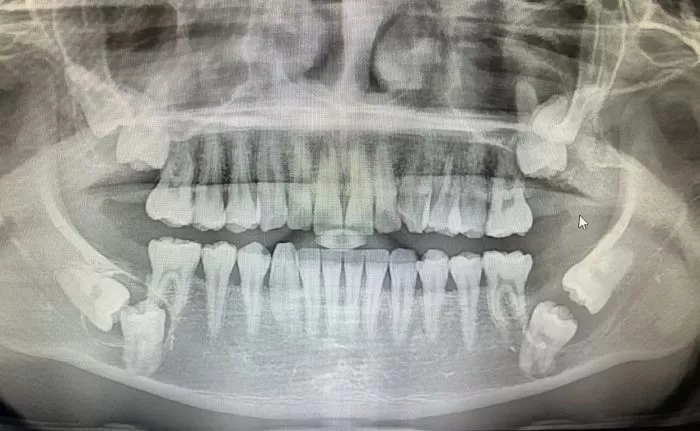

인사이트A씨의 사랑니 / 온라인 커뮤니티

[인사이트] 임우섭 기자 = 입속 치아 중 무려 8개의 치아가 매복돼 있는 사진이 나타나 충격을 주고 있다.

글에 따르면 작성자 A씨는 앞서 지난해 동네 치과에서 진찰을 받았다. 당시 치과 엑스레이 사진에서 치아 8개가 매복돼 있는 것을 발견했는데 치과의사는 작은 곳보다는 큰 병원에서 진찰을 받아야 할 것 같다며 대학병원을 추천했다.

대학병원 내에서 A씨 치아에 대해 진찰한 결과는 꽤 심각했다. 매복된 치아 중 4개는 사랑니이며 나머지 4개는 어금니였기 때문이다.

특히 잇몸 내 신경들이 다 눌려있는 상태로, 의사는 일부 이빨을 뽑게 될 시 구멍이 뚫릴 것이라고 말했다. 또 왼쪽 아래 한 부위는 염증이 아닌 물혹이라고 설명했다.